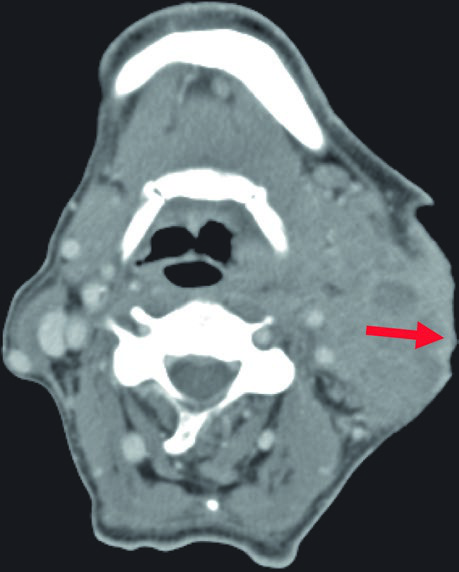

Dermal infiltration and bone involvement are findings that substantially alter the treatment plan. When there is clinical or radiological evidence of skin infiltration, the skin must be included as a target structure using bolus to ensure adequate surface dose. In cases with perioperative tumor spillage, the surgical scar also becomes part of the treatment volume.

Bone involvement requires specific assessment using bone windows on CT. The image shows periosteal reaction at the posterior aspect of the left mandibular ramus, suggesting direct involvement. When confirmed, the bony structure must be incorporated into the CTV with appropriate margin.

These findings highlight the importance of a thorough imaging study before simulation. The combination of soft tissue and bone windows on the same CT ensures that no tumor extension goes undetected.

When bone involvement is detected, the extent of mandibular irradiation must be carefully balanced against the risk of osteoradionecrosis (ORN). Including the involved bone segment with adequate margin is essential for local control, but extending CTV coverage unnecessarily into healthy mandibular bone increases ORN risk without oncologic benefit. The use of dose painting — delivering higher doses to the involved segment while limiting dose to uninvolved bone — can help achieve this balance when IMRT or VMAT techniques are available.

In my experience, integrating MRI findings — especially fat-saturated sequences — with the simulation CT significantly improves delineation confidence in these complex cases.